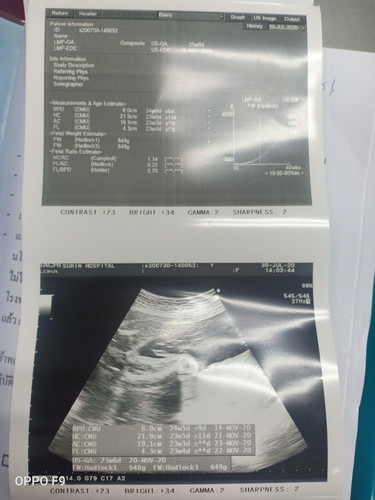

ลูกผู้หญิงหรือชาย

แม่ๆช่วยดูหน่อยค่ะ ว่าได้ลูกผู้หญิง หรือ ผู้ชายค่ะ 😍😍

ลูกสาวจ้า